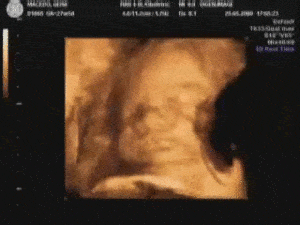

Ecografia Ostetrica bidimensionale e 3D-4D

Durante la gravidanza è consigliabile l’esecuzione di almeno tre esami ecografici da effettuarsi rispettivamente nel primo, nel secondo e nel terzo trimestre.